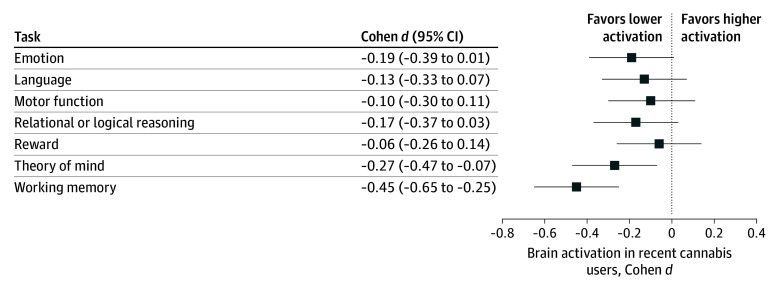

For graphical comparison, we calculated effect sizes (Cohen d) for activation during each task by (1) lifetime history of use (heavy users vs nonusers), (2) recent use (THC-positive vs THC-negative result), and (3) cannabis diagnosis (history vs no history of dependence). We report comparisons between nonusers and moderate users, as well as heavy users and moderate users, in eFigures 2 and 3 in Supplement 1.

The comparison of individuals with positive vs negative THC test results revealed lower brain activation in recent cannabis users for the working memory and the theory of mind tasks. However, in the full model, the associations for the theory of mind task no longer remained after adjusting for race and education, because both of these variables were associated with a positive THC test result and also with task activation (eTables 10 and 11 in Supplement 1). After adjusting for associations with lifetime use, the working memory and motor tasks showed associations between recent cannabis use and activation levels but these did not survive false discovery rate correction. A summary of effect sizes for brain activation and positive vs negative urine samples is illustrated in Figure 3, and central tendency by group is reported in eTable 9 in Supplement 1. No task showed an association with diagnosis of cannabis dependence (eFigure 1 and eTable 12 in Supplement 1).